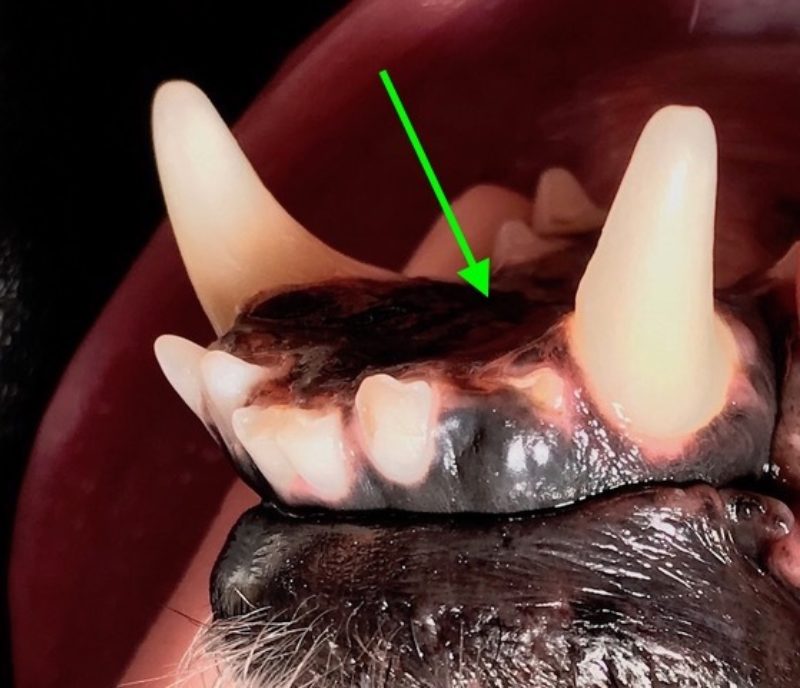

Der hübsche neun Jahre alte schwarze Mischlingsrüde Nando aus Italien wird vorgestellt, da die Besitzerin Zahnstein und einen unangenehmen Geruch aus der Maulhöhle festgestellt hat. Während der Untersuchung werden folgende Befunde erhoben: mittelgradiger Zahnstein an den meisten Zähnen, im Unter- und Oberkiefer je ein abgebrochener Schneidezahn (Abb. 1 und 2) und eine große „Zahnlücke“ im Unterkiefer rechts (Abb. 3). Hier scheinen die drei letzten Backenzähne zu fehlen. Nando ist ein sportlicher und schlanker Hund. Sein Herz schlägt regelmäßig und ohne Nebengeräusche. Dennoch untersuchen wir vor der Operation sein Blut, um mögliche Anästhesierisiken weitgehend ausschließen zu können. Wenige Tage später werden Nandos Zähne in Narkose sorgfältig von Zahnstein befreit und anschließend poliert. Von den beiden abgebrochenen Schneidezähnen und dem Bereich der vermeintlichen Zahnlücke im Unterkiefer werden Röntgenbilder angefertigt. Die Kronen der beiden Schneidezähne sind so tief abgebrochen, dass die Pulpahöhle offen liegt (Abb. 4). Im Bereich der „Zahnlücke“ zeigt das Röntgenbild Wurzelanteile nicht vollständig vorhandener oder vielleicht auch nicht vollständig ausgebildeter Zähne (Abb. 5).

Vorgehen bei den abgebrochenen Schneidezähnen

In der Pulpa verlaufen die Blut- und Nervengefässe eines Zahnes. Da die Schneidezähne von „Nando“ so tief abgebrochen sind, dass Blut und Nervengefäße nicht mehr durch die Schicht des Dentins und des Zahnschmelzes vor einem Kontakt mit der Außenwelt geschützt sind, ist eine Behandlung unbedingt erforderlich. Denn zum einen besteht die Gefahr einer Infektion, und zum anderen ist beim Tier in diesem Fall genauso wie beim Mensch mit Zahnschmerzen zu rechnen. Eine aufwändige Wurzelbehandlung, die für abgebrochene oder anderweitig erkrankte Zähne auch beim Tier möglich ist, scheint im Fall der funktionell wenig bedeutsamen Schneidezähne nicht gerechtfertigt. Daher ziehen wir bei „Nando“ die beiden abgebrochenen Schneidezähne in der Vollnarkose.